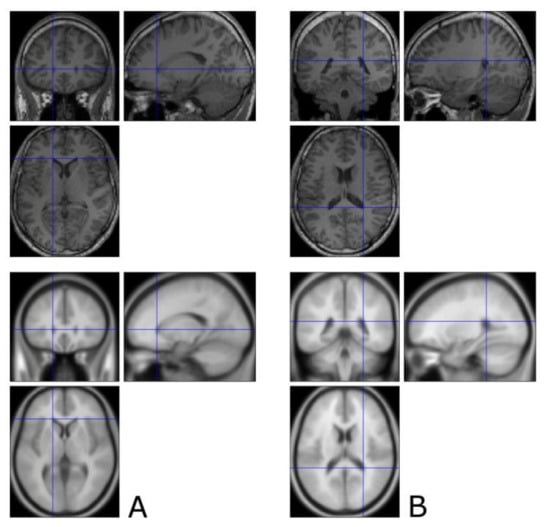

3.1. The Corticospinal Tract